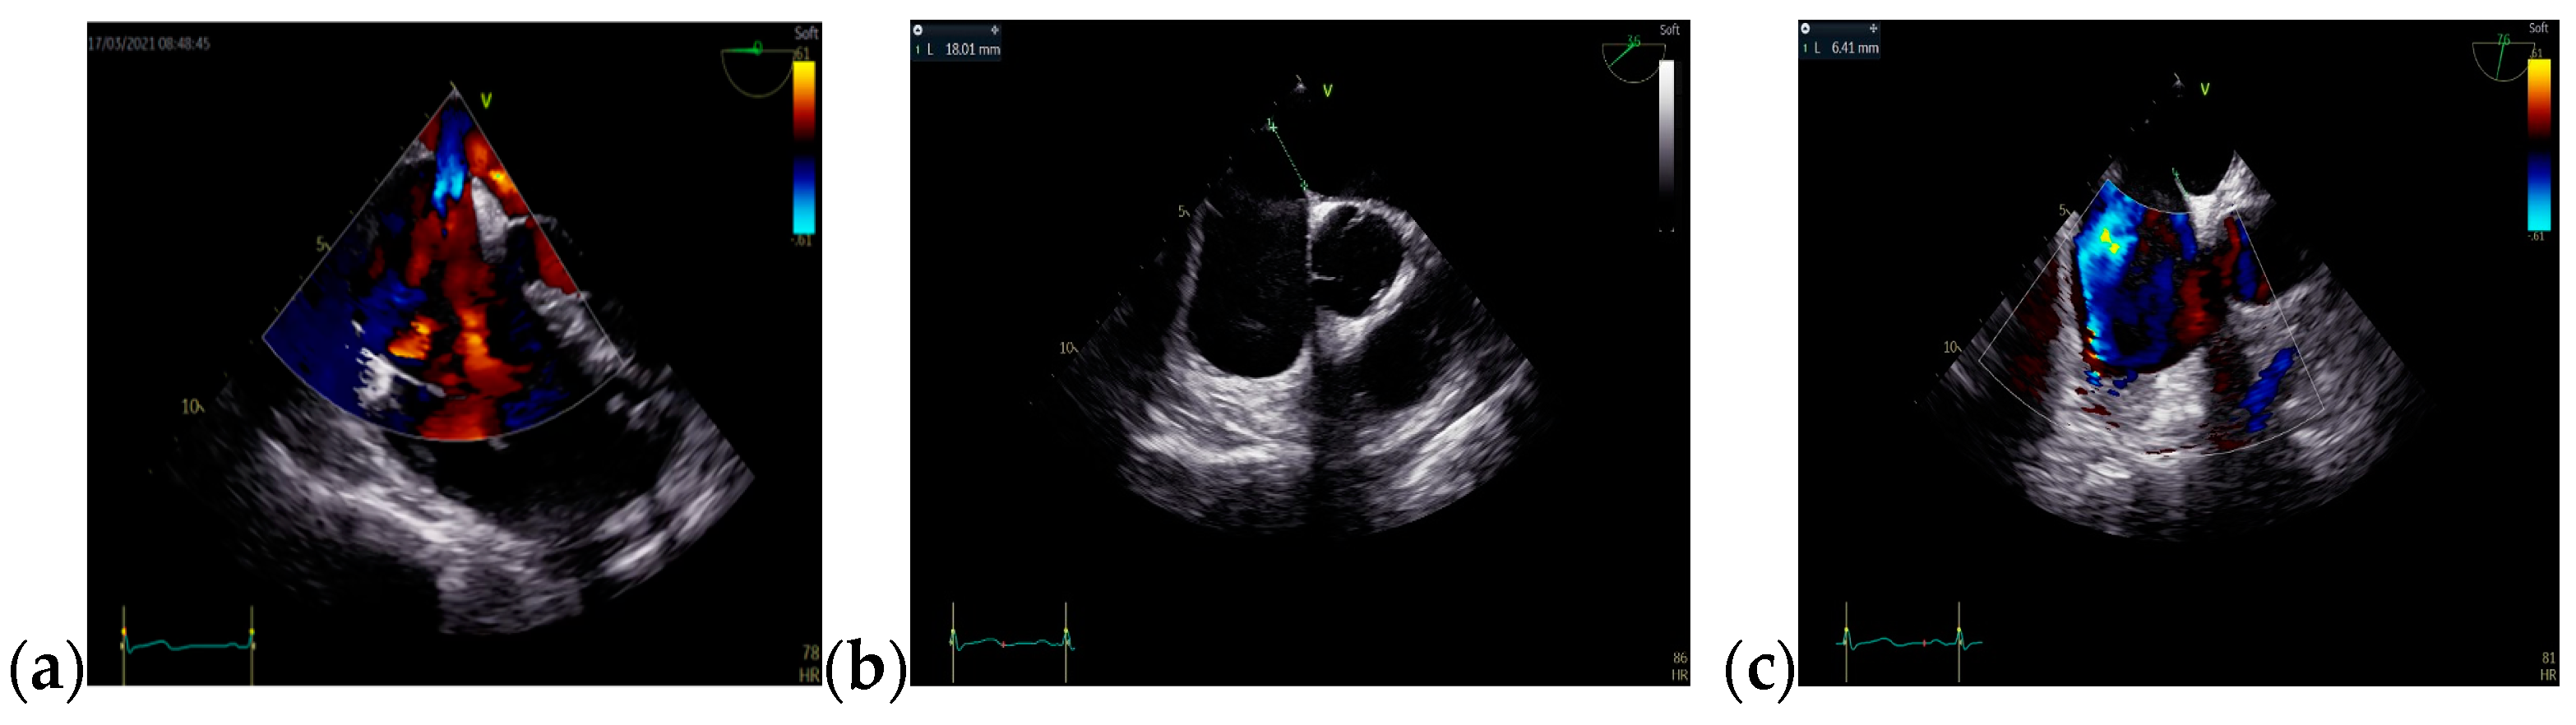

Due to the patient’s symptomatology, clinical features. and suspected findings from the TTE, including increased Qp/Qs ratio, a TOE was required and revealed an OSASD, with a diameter of 1.8 cm and aortic rim of 6.4 mm (Figure 4).

Figure 4.

TOE: (a) Mid-esophageal 4-chamber view: turbulent color Doppler flow at the level of the interatrial septum; (b) Mid-esophageal short-axis view: atrial septal defect with a diameter of 1.8 cm (18 mm); (c) Mid-esophageal short-axis view: aortic rim = 6.4 mm. Abbreviations: TOE—Transesophageal echocardiography.